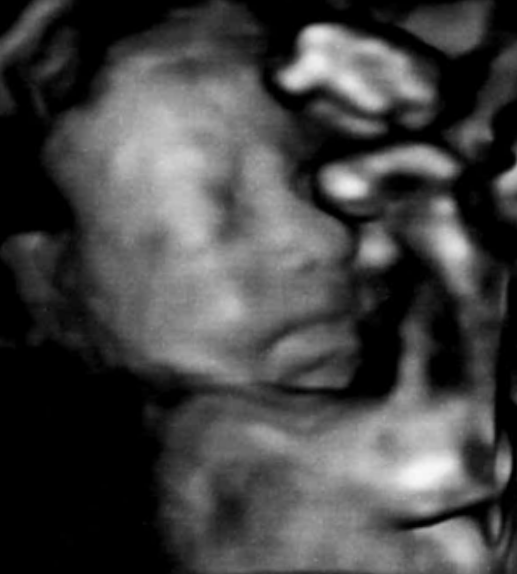

助産師による4Dエコーのご案内

赤ちゃんのかわいらしい様子をゆっくり見ることができます

ご家族の方も同席し、お話を聞いていただくこともできます

対象者

妊娠14週以降の妊婦さんとご家族

※お子さんも一緒にエコーを見ることができます

料金

2,000円(税込)

ご予約・問い合わせ:産婦人科外来

TEL0143-24-1331

【電話受付】平日 13:00~15:00

【予約枠】火~金曜日 12:00~14:30(最終受付14:00)

1枠30分の完全予約制となります